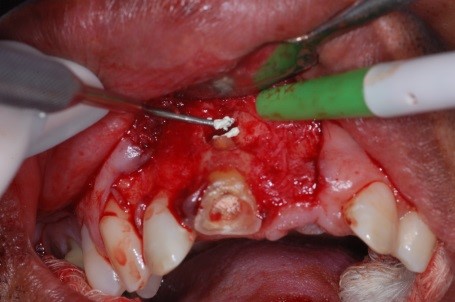

O retalho escolhido foi de um paciente. A incisão foi efetuada com lâmina de bisturi nº 15. O retalho foi elevado. Foi realizada a osteotomia com broca de alta rotação da série 700, para ter acesso à região periapical. A lesão foi curetada com curta.

Com a broca foi realizada uma apicectomia e foram removidos 2 mm de ápice. A cavidade para retrobturação foi preparada com broca esférica, sempre sob irrigação com soro fisiológico, e então se realizou retrobturação.

O material retrobturador utilizado foi o MTA. Após a condensação do material na cavidade, removeram-se os excessos com uma cureta periodontal.

- Figura 10 – Corte do ápice radicular com broca de alta da série 700.

- Figura 14 – Remoção dos cones extras pré-existentes.

- Figura 15 – Colocação do material MTA.